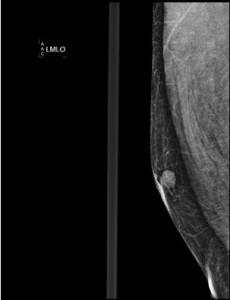

Justificación: La prueba indicada es la mamografía. Esta prueba, es la técnica de elección para la aproximación inicial en el diagnóstico de la patología mamaria. Tiene que realizarse la proyección cráneo-caudal y oblicuo medio-lateral para así poder localizar espacialmente dónde se encuentra la lesión, si es que hay.

Haz click en las imágenes para verlas ampliadas